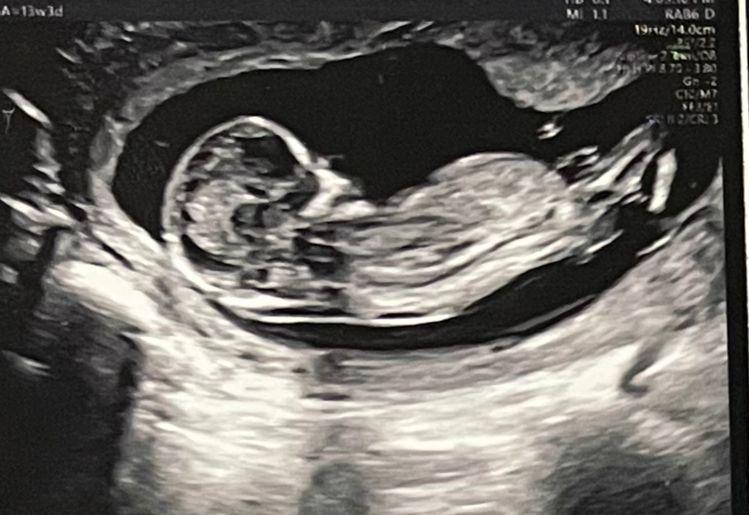

Ana went in for the ultrasound at Motherhood and my heart was in my mouth when the nurse came out in a matter of minutes. I then realised she came to call me in as well. This was the first time I’d be in the room for the ultrasound. The previous ones, at other hospitals, didn’t allow me in.

When the Dr started, we heard the heartbeat for the very first time. It was music to my ears, the best thing I had ever heard till date. Tears rolled down my face with joy and I almost jumped off my stool to hug the doctor! We were over the moon!